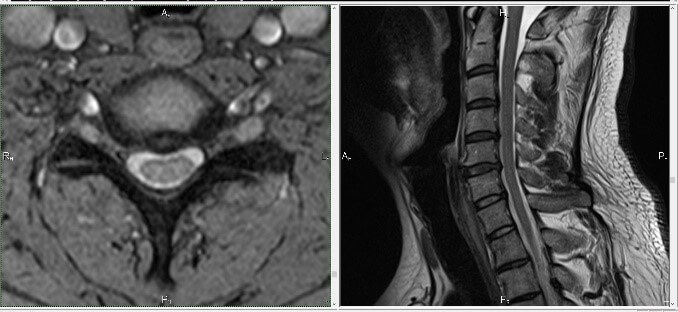

Плотное расположение шеи затрудняет диагностику местных заболеваний — рутинными методами зачастую не удается выявить проблему. Поэтому в большинстве случаев рекомендуется проводить МРТ шеи при необходимости детальной диагностики.

Обычно МРТ шеи применяется, когда необходимо оценить состояние шейного отдела позвоночника, определить содержимое позвоночного канала. Как магнитно-резонансная ангиография, эта процедура показана для диагностики кровеносных сосудов, обеспечивающих приток крови к мозгу.

Обследование позволяет диагностировать грыжи и грыжи, показать состояние щитовидной железы, лимфатических узлов, гортани и спинного мозга в этой области.

На фото мягких тканей шеи врач способен учесть следующие патологические явления:

- кистозная масса, абсцесс;

- новообразования доброкачественного или злокачественного характера;

- метастазы;

- синяки;

- инородные тела;

- Патологии органов шеи (щитовидной железы, слюнных желез, гортани и др.).